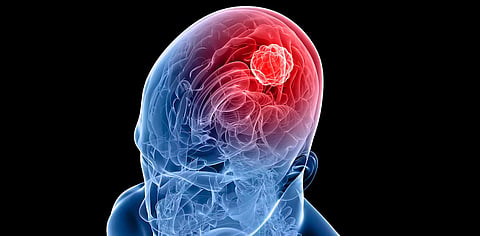

BENGALURU: World Brain Tumour Day is an international commemoration day observed annually on June 8 with the aim of raising awareness about brain tumours and educating people about the signs and symptoms of the disease. Experts opine that lifestyle choices increase the risk of developing brain cancer.

Dr. Sridhar PS, MBBS, MD (Radiotherapy), DNB (Radiotherapy) at HCG Cancer Centre, Bengaluru, stated that environmental factors and lifestyle choices such as chemical exposure, radiation, smoking, and unhealthy diets increase the risk of developing brain tumours.

"The occurrence of brain tumour cases in India is steadily rising. The rise can be attributed to advancements in diagnostic techniques, increased access to medical care, heightened public awareness, and the influence of environmental and lifestyle factors. The main symptoms of brain tumours are unexplained headaches, long-standing headaches, neurological deficits, and increased projectile vomiting," Dr. Sridhar explained.

Dr. Ganesh Veerabhadraiah, Senior Consultant Brain and Spine, Neuroendovascular Surgery, Fortis Hospital, Cunningham Road, Bengaluru, said the most common types of brain tumours can be classified into two groups: non-cancerous (non-malignant) and cancerous.

According to the International Association of Cancer Registries (IARC), there are approximately 28,000 cases of brain tumours reported every year. This translates to an incidence rate of 5–10 cases per 100,000 people in India.

Additionally, brain tumours account for 2 percent of all malignancies diagnosed in the region, Dr. Ganesh explains.